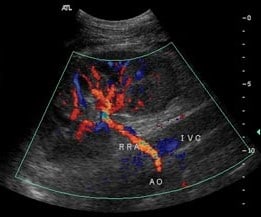

Imaging procedure as shown in the photograph below in twins is used for ?

| A |

Twin to twin transfusion. |

|

| B |

Conjoined twin. |

| C |

Diagnosis of twins. |

| D |

All of the above. |